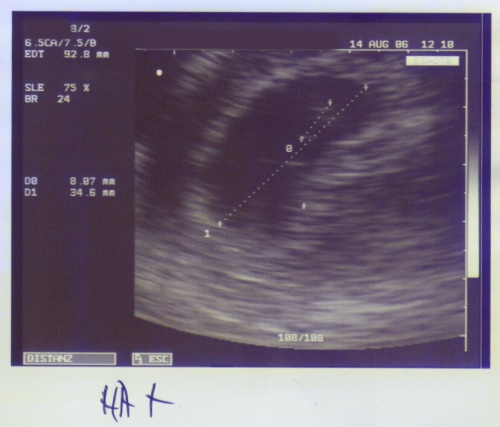

Schon 8 mm groß!

Knapp 26 mm - in anderthalb Wochen um das dreifache gewachsen - Wahnsinn!